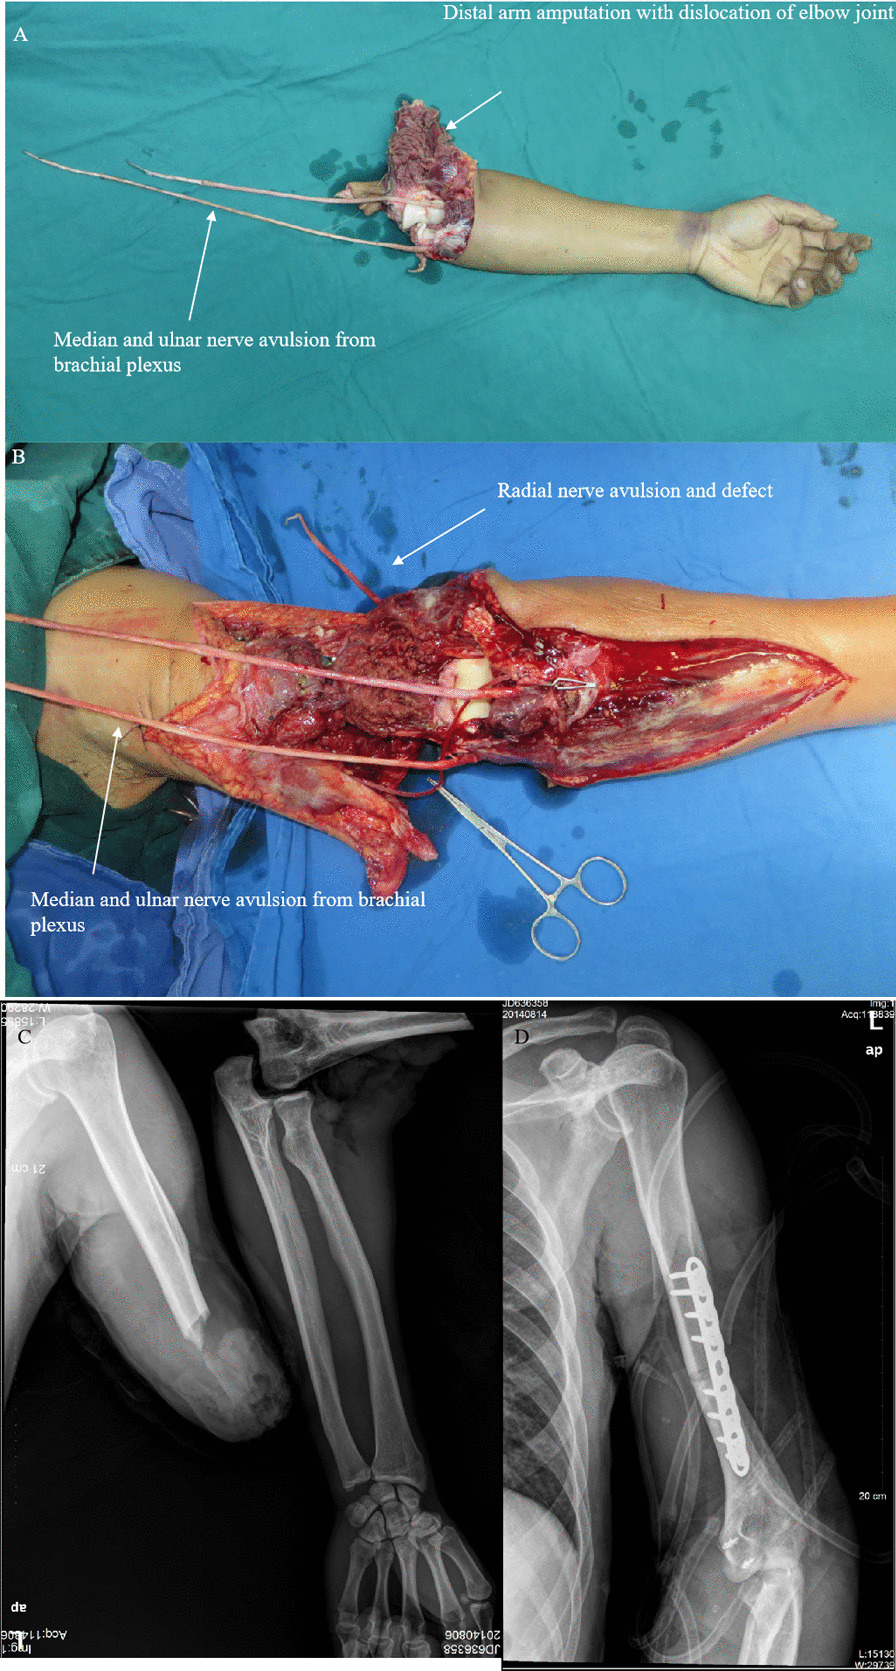

Figures 3, 4, 5 and 6 summarize the treatment process of a patient (case 1) undergoing M-(M + R) repair. For this patient, nerve merging repair and upper limb replantation were performed simultaneously. To maximize the repair outcome and reach a balance between the extensor carpi, finger extensors, flexor carpi, and finger flexors, the UN was designed to be sacrificed to repair the RN and MN. As such, M-(M + R) repair was employed for this patient. After nerve regeneration, the MN innervated the distal ends of the MN and RN.

Fig. 3.

A patient (case 1) undergoing M-(M + R) repair (Part 1). A The left upper arm was severed, which was accompanied by dislocation of the elbow joint and avulsion of the three nerves with defects. B Temporary blood circulation was provided to shorten the warm ischaemia time, elbow joint reduction was performed, and the ligament was repaired. C Preoperative X-ray showed fractures in the distal humerus segment and dislocation of the elbow joint. D Postoperative X-ray showed internal fixation of the humeral fractures, reduction of the elbow joint, and implantation of anchor nails to repair the ligament